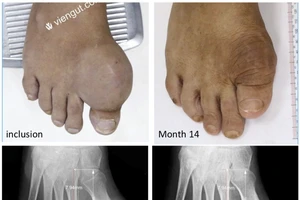

Viện Gút TP.HCM điều trị khỏi bệnh gút theo tiêu chuẩn nào?